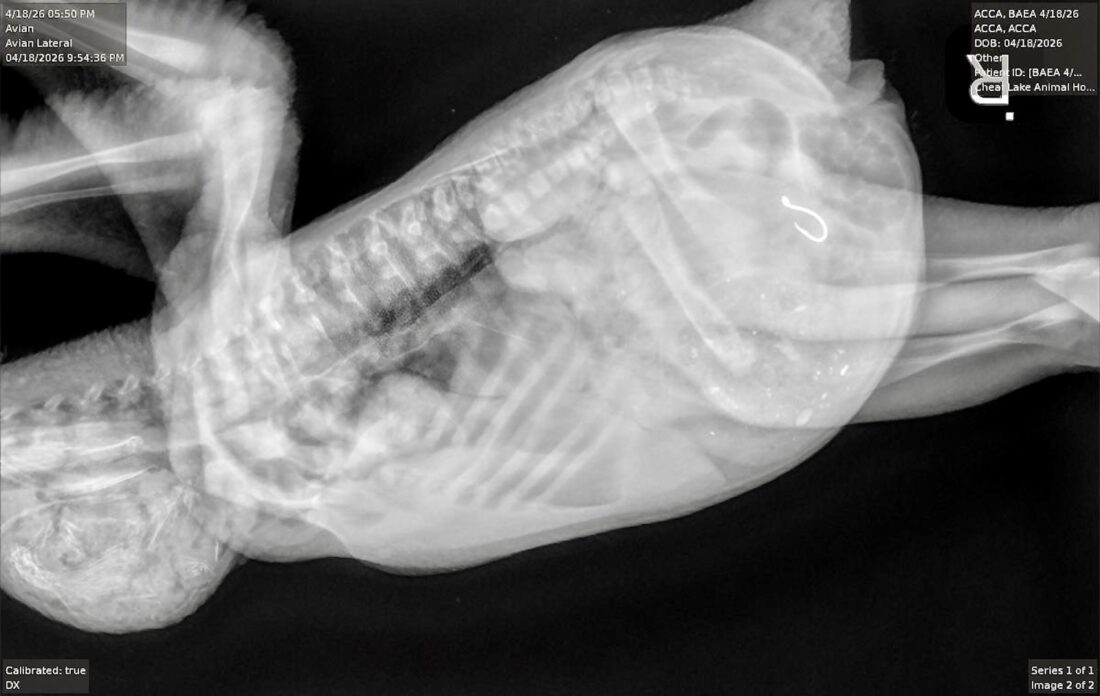

- The baby eagle’s X-ray shows the fishhook. (Photo courtesy Tricia Mayle, Avian Conservation Center of Appalachia)

The baby eagle's X-ray shows the fishhook. (Photo courtesy Tricia Mayle, Avian Conservation Center of Appalachia)